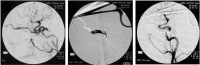

A carotid-cavernous fistula (CCF) is an abnormal communication between arteries and veins within the cavernous sinus and may be classified as either direct or dural. Direct CCFs are characterized by a direct connection between the internal carotid artery (ICA) and the cavernous sinus, whereas dural CCFs result from an indirect connection involving cavernous arterial branches and the cavernous sinus. Direct CCFs frequently are traumatic in origin and also may be caused by rupture of an ICA aneurysm within the cavernous sinus, Ehlers-Danlos syndrome type IV, or iatrogenic intervention. Causes of dural CCFs include hypertension, fibromuscular dysplasia, Ehlers-Danlos type IV, and dissection of the ICA. Evaluation of a suspected CCF often involves non-invasive imaging techniques, including standard tonometry, pneumotonometry, ultrasound, computed tomographic scanning and angiography, and/or magnetic resonance imaging and angiography, but the gold standard for classification and diagnosis remains digital subtraction angiography. When a direct CCF is confirmed, first-line treatment is endovascular intervention, which may be accomplished using detachable balloons, coils, liquid embolic agents, or a combination of these tools. As dural CCFs often resolve spontaneously, low-risk cases may be managed conservatively. When invasive treatment is warranted, endovascular intervention or stereotactic radiosurgery may be performed. Modern endovascular techniques offer the ability to successfully treat CCFs with a low morbidity and virtually no mortality.